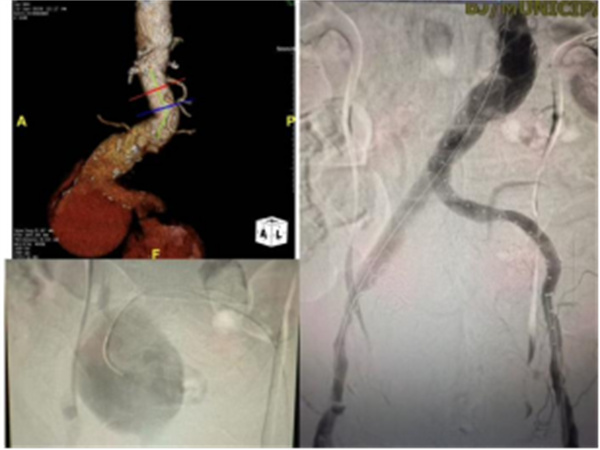

急诊科医护人员根据临床经验和检验结果判断,高度怀疑为腹主动脉瘤破裂。这是一种血管外科急症,抢救窗口期极短。为全力抢救患者生命,医院急诊科立即启动双重应急流程:介入与血管外科急会诊、急诊主动脉CTA检查。医院放射科紧急开通绿色通道同步响应。检查在5分钟内完成,确诊为腹主动脉瘤破裂。

在患者经由急诊绿色通道直送导管室后,由杨永久、丁旭、郑新颖以及导管室技师护士组成的治疗团队随机开始急诊抢救手术。术中,患者仅能在高剂量血管活性药物支持下将血压维持在100mmHg左右,手术操作难度大。团队依次完成病变血管评估、髂内动脉栓塞、支架主体及髪支支架植入。术中探查发现,患者除主髂动脉瘤破裂出血外,腹壁下动脉和旋髂浅动脉仍在持续向右侧破裂的髂动脉瘤腔供血,属隐蔽性出血源。杨永久果断采用微导管超选择技术,精确定位并封堵两支出血血管,完成主髂动脉腔内隔绝治疗。